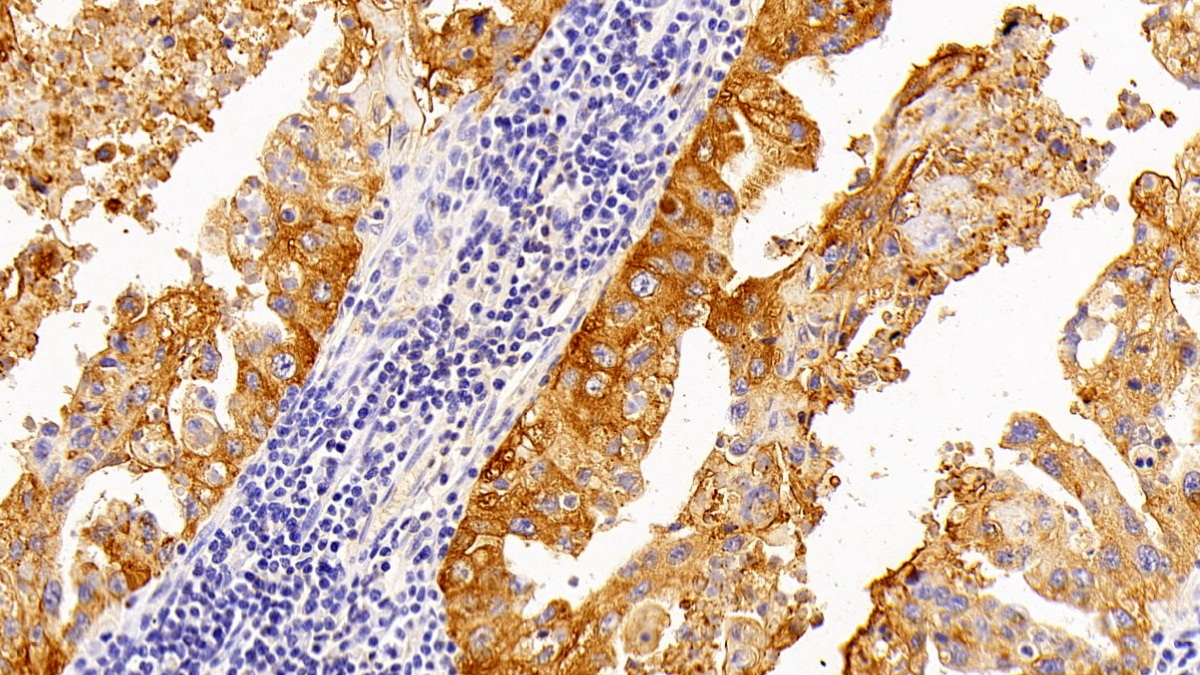

DAB staining on IHC-P; Samples: Human Lung cancer Tissue; Primary Ab: 10μg/ml Rabbit Anti-Human SPA2 Antibody Second Ab: 2μg/mL HRP-Linked Caprine Anti-Rabbit IgG Polyclonal Antibody (Catalog: SAA544Rb19)